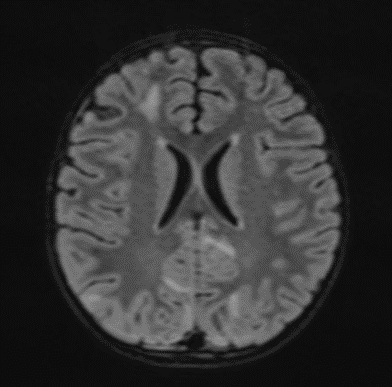

The changes observed are characteristic radiological markers appreciated on DWI, indicative of cytotoxic edema. The DWI changes are considered reliable early signs of acute toxic encephalopathy, specifically methotrexate-related leukoencephalopathy. Post-contrast MR images did not show any abnormal contrast enhancement.

Picture 4.

Edema and Cytotoxic Edema: The superior parietal lobes showed suspected zones of cytotoxic edema. This was further supported by the presence of diffusion-weighted imaging (DWI) changes, characterized by restricted diffusion, a hallmark of cytotoxic edema. These findings align with the pathophysiology of MTX-LE, where MTX-induced neuronal damage leads to cellular swelling and subsequent restricted diffusion.

The early identification of MTX-LE is critical for timely intervention. The presence of characteristic DWI changes, even in the absence of clinical symptoms, should prompt consideration of MTX-LE (7). In this case, the patient’s neurological deterioration and convulsions underscored the need for immediate imaging and clinical intervention. The absence of abnormal contrast enhancement on post-contrast MR images suggests that MTX-LE can present without blood-brain barrier disruption, further complicating diagnosis without advanced imaging modalities.